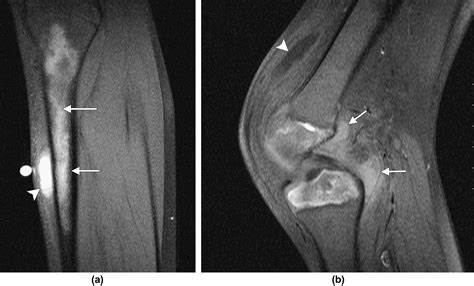

MRI Extremely High Detects bone marrow edema, which is often the earliest sign of stress, infection, or infarction.

💡 Note: In cases where the initial imaging is unclear, doctors often rely on MRI scans, as they are exceptionally sensitive to early changes in bone marrow, which are often the first indicator of many acute bone pathologies.